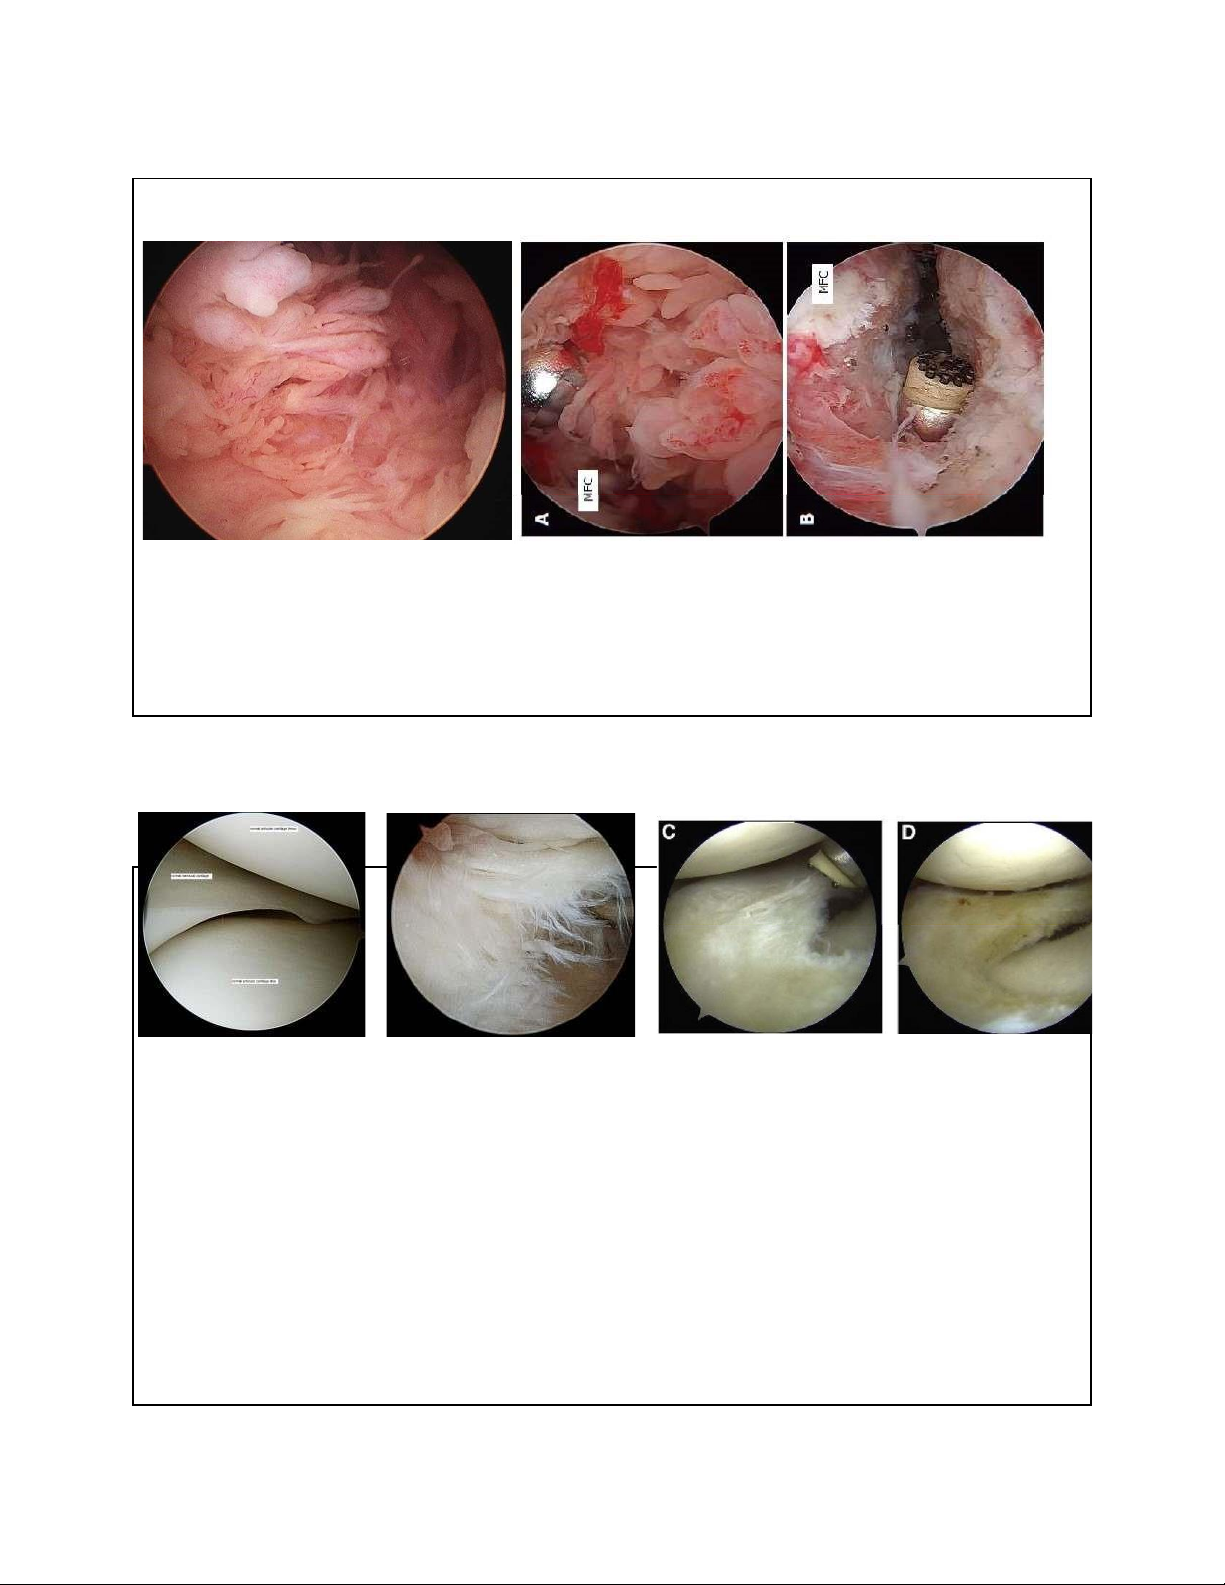

2. RÁCH SỤN CHÊM – KHÂU SỤN CHÊM 9

2. RÁCH SỤN CHÊM – CẮT LỌC SỤN CHÊM 10 lOMoAR cPSD| 22014077 7/15/2023 3. TỔN THƯƠNG DÂY CHẰNG

CẮT LỌC HOẠT MẠC VIÊM 20

SỬA CHỬA TỔN THƯƠNG SỤN CHÊM SỤN KHỚP 21 lOMoAR cPSD| 22014077 7/15/2023 Lấy bỏ chuột khớp 22 microfracture • Dễ dàng thực hiện • Kinh tế